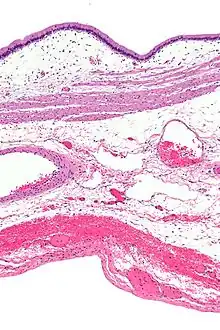

Microanatomy

The gallbladder wall is composed of a number of layers. The innermost surface of the gallbladder wall is lined by a single layer of columnar cells with a brush border of microvilli, very similar to intestinal absorptive cells.[2] Underneath the epithelium is an underlying lamina propria, a muscular layer, an outer perimuscular layer and serosa. Unlike elsewhere in the intestinal tract, the gallbladder does not have a muscularis mucosae, and the muscular fibres are not arranged in distinct layers.[6]

The mucosa, the inner portion of the gallbladder wall, consists of a lining of a single layer of columnar cells, with cells possessing small hair-like attachments called microvilli.[2] This sits on a thin layer of connective tissue, the lamina propria.[6] The mucosa is curved and collected into tiny outpouchings called rugae.[2]

A muscular layer sits beneath the mucosa. This is formed by smooth muscle, with fibres that lie in longitudinal, oblique and transverse directions, and are not arranged in separate layers. The muscle fibres here contract to expel bile from the gallbladder.[6] A distinctive feature of the gallbladder is the presence of Rokitansky–Aschoff sinuses, deep outpouchings of the mucosa that can extend through the muscular layer, and which indicate adenomyomatosis.[7] The muscular layer is surrounded by a layer of connective and fat tissue.[2]

The outer layer of the fundus of gallbladder, and the surfaces not in contact with the liver, are covered by a thick serosa, which is exposed to the peritoneum.[2] The serosa contains blood vessels and lymphatics.[6] The surfaces in contact with the liver are covered in connective tissue.[2]